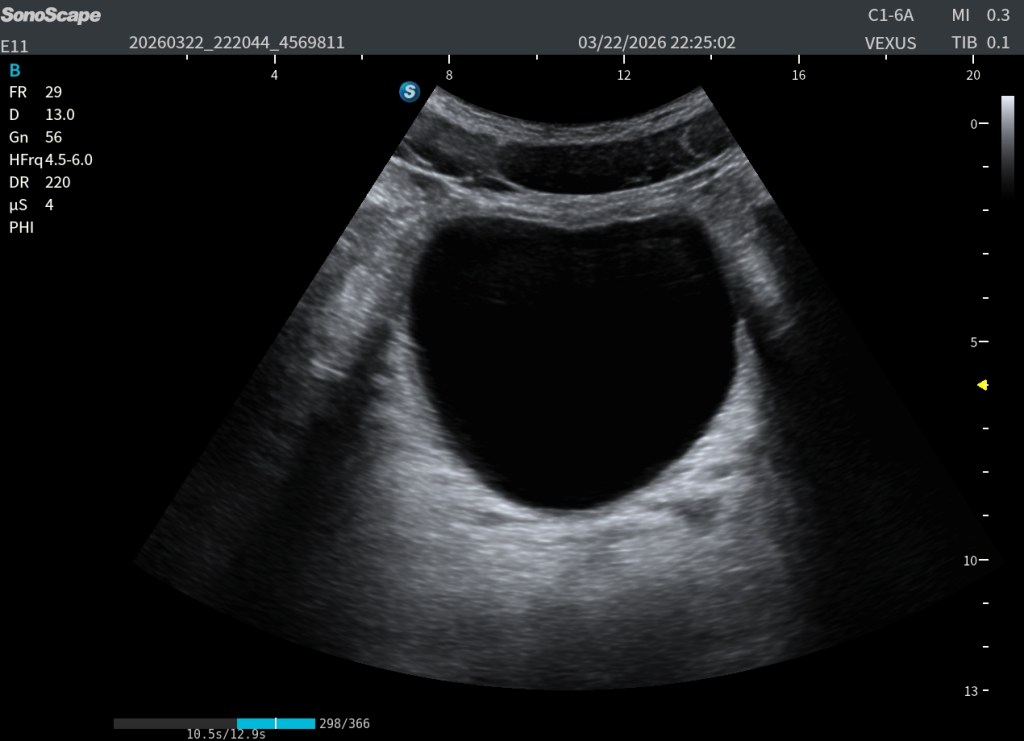

🔧 ¿Qué hacemos con la LGC?

Aquí es donde la LGC cambia completamente la imagen.

En lugar de intentar compensar con TGC o bajar la ganancia global (lo cual empeora otras zonas), utilizamos la LGC de forma selectiva:

- Mantenemos los potenciómetros laterales en valores normales

- Reducimos los potenciómetros centrales

👉 ¿Qué conseguimos?

- Disminuir el exceso de brillo del refuerzo posterior

- Eliminar los ecos falsos dentro de la vejiga

- Mejorar la homogeneidad global

- Recuperar estructuras posteriores

El resultado es una imagen mucho más limpia, más equilibrada y, sobre todo, más diagnóstica.

👁️ Lo que deberías ver

Cuando la LGC está bien ajustada:

- La vejiga sigue siendo anecoica, sin “ruido interno”

- El refuerzo posterior deja de ser exagerado

- El campo posterior se vuelve visible

- Y estructuras como las vesículas seminales aparecen con claridad

Este punto es clave: no se trata solo de “hacer la imagen más bonita”, sino de no perder información clínica relevante.